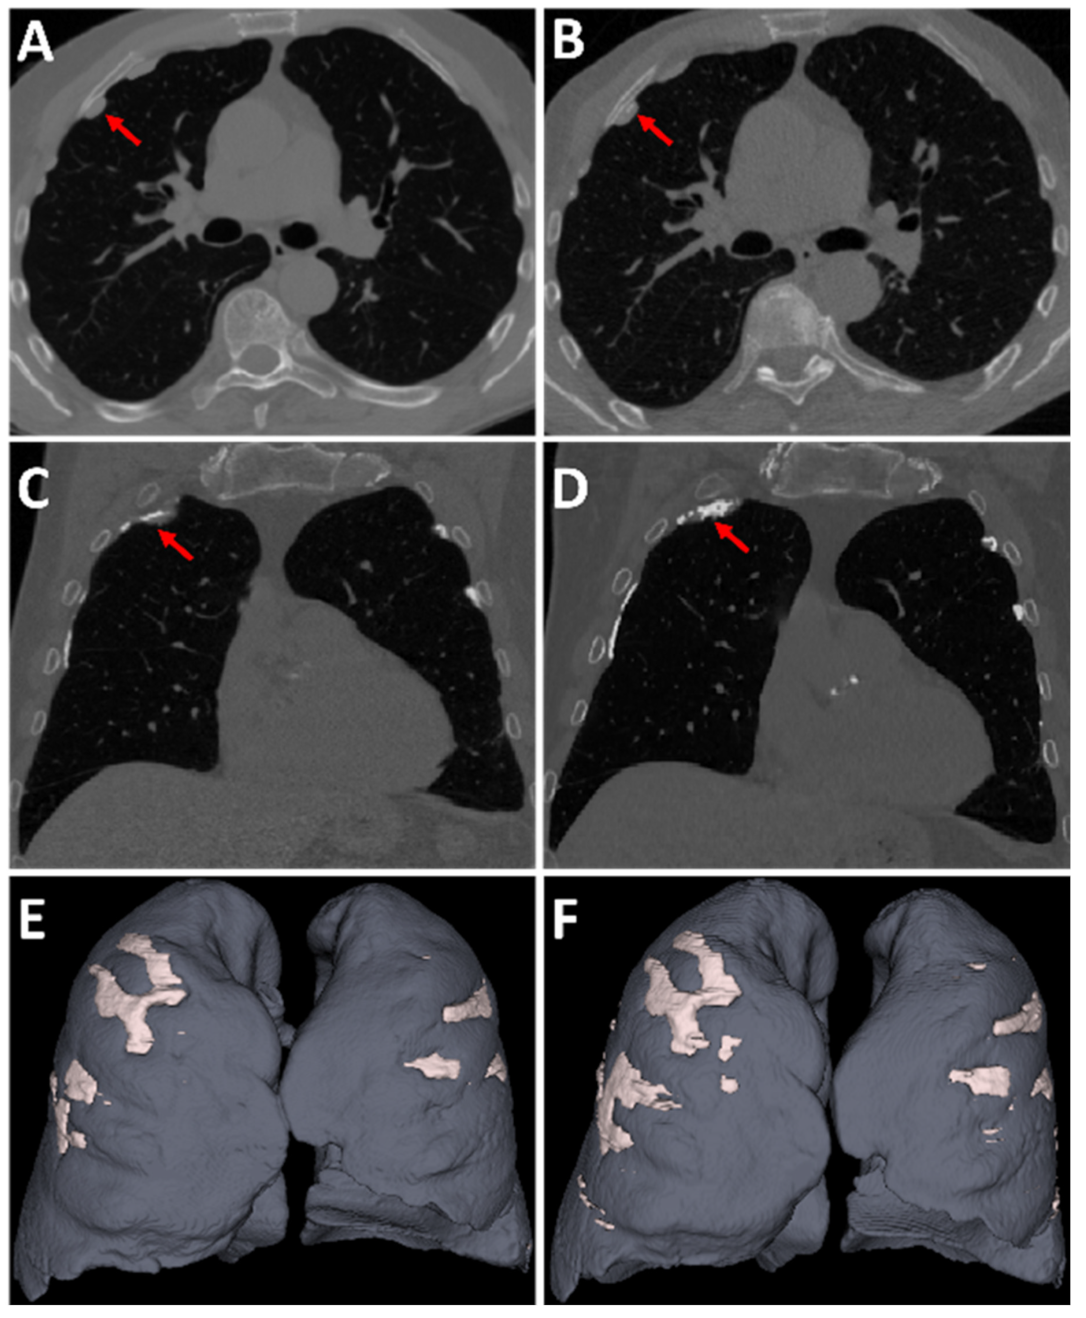

2.4. Data

2.5. Chest CT Scans Visual Analysis

3.4. Longitudinal Comparison of Pleural Plaques Volume Progression